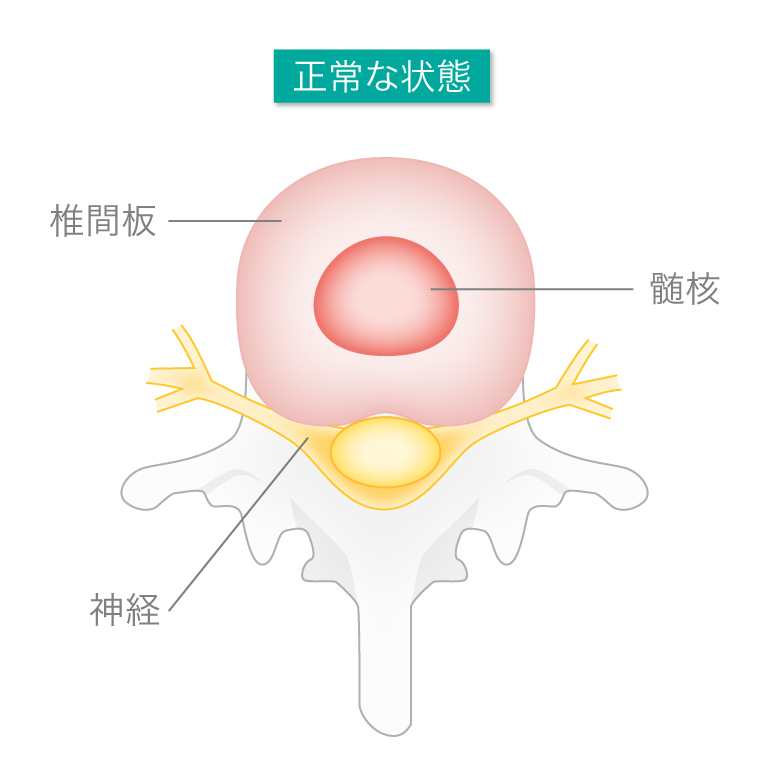

椎間板ってなんですか?

「椎間板」とは、わたしたちの身体を支える首から腰までの骨を連結させている「骨と骨の間の組織」のことを言います。椎間板の中心には核と呼ばれるゲル状の「髄核(ずいかく)」と髄核を取り囲む柔らかい組織の「線維輪(せんいりん)」の二重構造になっています。

椎間板はクッションのような働きをしていて、背骨にかかる圧力を分散させ、衝撃を吸収。さらに上下の骨を支えたり、お辞儀や体をひねったりという身体の動きに関与している場所です。